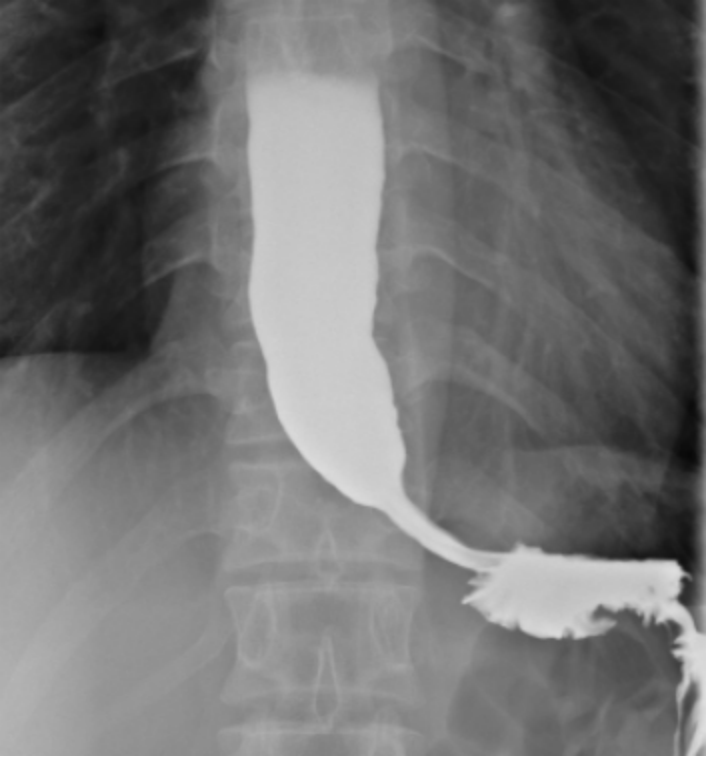

经过胃镜、食管造影等一系列检查,医生发现患者食管明显扩张,里面还有未排出的食糜残留,贲门部位狭窄,胃镜通过时阻力很大。

尤其是食管造影的结果,呈现出典型的 「鸟嘴样」狭窄——这正是贲门失弛缓症的特征性表现。

动态观察食管下段神似"鸟嘴」